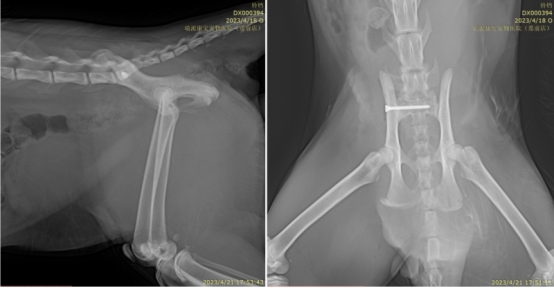

一只2岁7个月的雄性英国短毛猫,从8楼高处坠落,出现尿血、呼吸急促及右前肢与骨盆区严重功能障碍。接诊后,吴泉太院长立即启动多系统评估。X线检查显示右侧肱骨远端粉碎性骨折、髋关节脱位伴髂骨前移;血液检测提示高血糖、肾功能异常及红细胞增多,综合确诊为“高坠综合征伴多发性骨折与脏器损伤”。

面对这一危及生命的复杂创伤,吴院长制定了分期治疗方案:优先稳定生命体征,通过静脉补液纠正脱水与电解质紊乱,同时实施强效镇痛与抗生素预防感染。待患猫状况稳定后,随即开展骨科重建手术——包括右侧肱骨骨折内固定术、髋关节复位与髂骨稳定术,精准恢复骨骼结构与关节对位。

该病例的难点不仅在于多处骨折与脱位的精准复位,更在于全身多系统损伤背景下,如何平衡手术时机、控制感染风险并促进组织愈合。吴院长通过骨科手术与内科支持的协同管理,实现了创伤修复与全身稳定的双重目标。

术后3周复查显示,骨折部位愈合良好,关节功能逐步恢复,血液指标恢复正常,精神与食欲明显改善。这也充分体现了吴泉太院长拥有在严重创伤救治中的综合决策能力,既能通过精准的骨科技术重建骨骼结构,又能依托全面的内科管理为复杂创伤患者创造最佳康复条件。